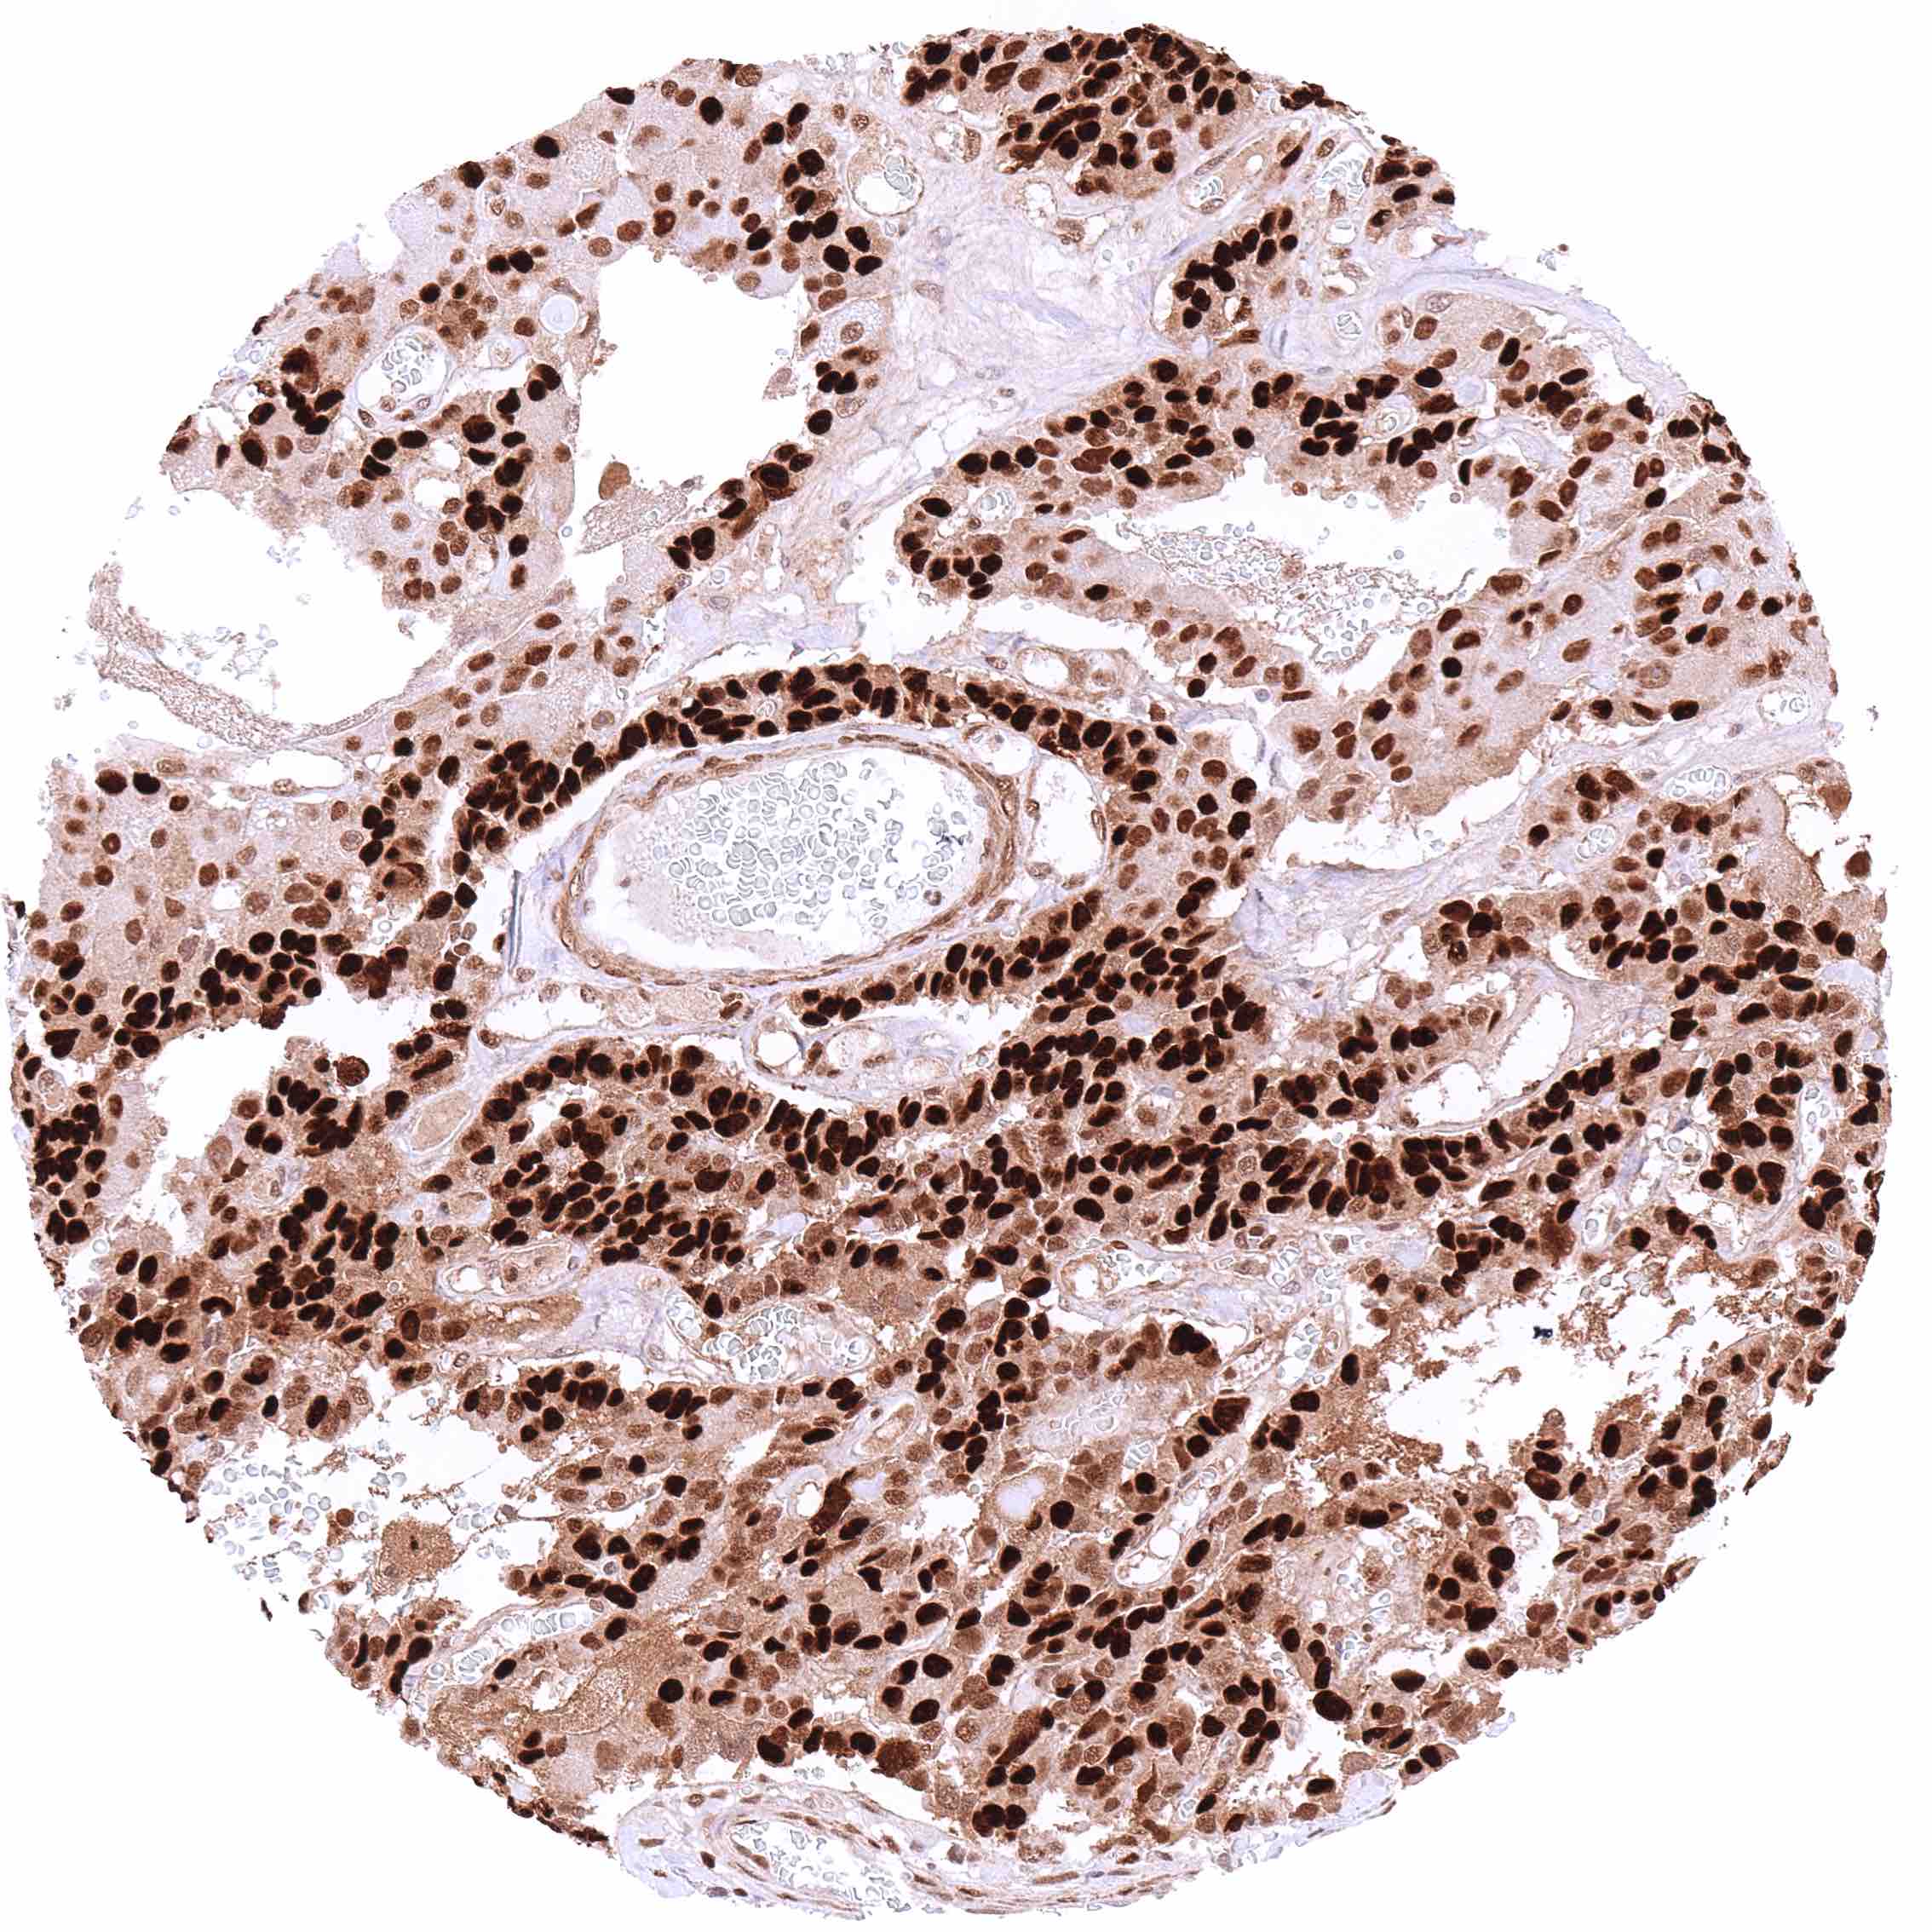

Urinary bladder – Muscle-invasive urothelial carcinoma with moderate to strong, predominantly nuclear p27 staining of tumor cells.